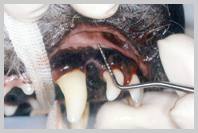

| Probing

103 to demonstrate 8mm deep pocket on bucco-caudal aspect |